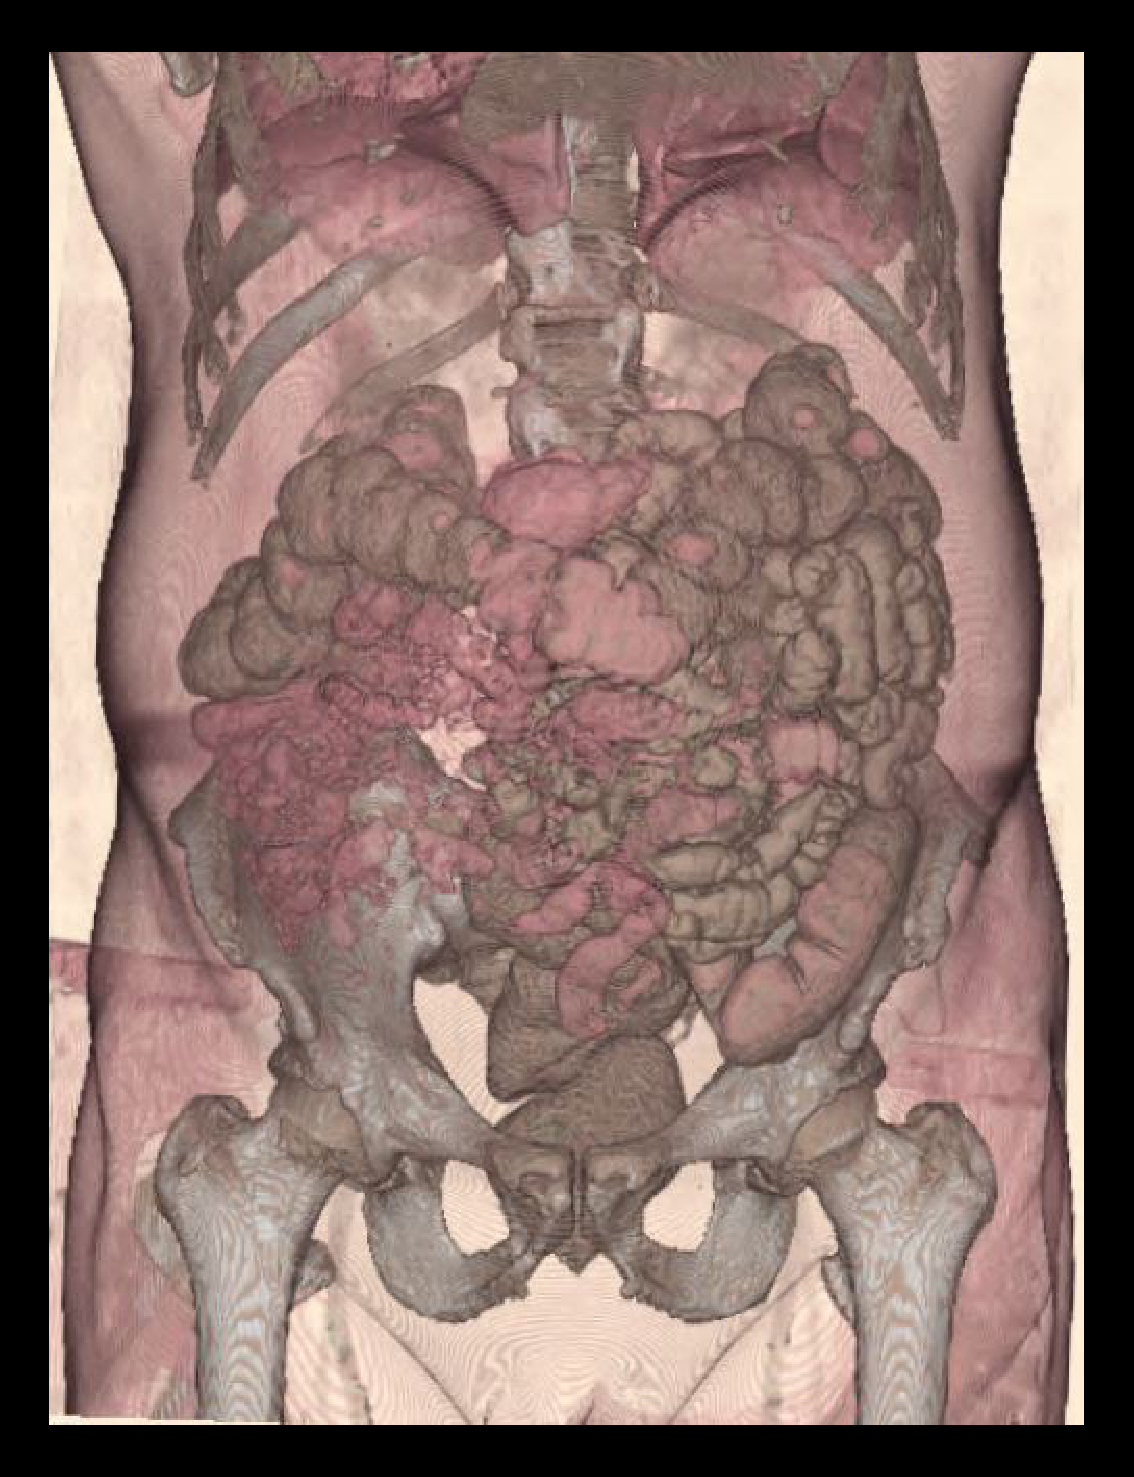

CT multiphase abdomen is mainly helpful in the detection of conditions within the abdominal cavity, such as neoplasms, trauma, congenital abnormalities, and for surgical planning. Contrast media is used for this scan to recognize and categorize pathologies.